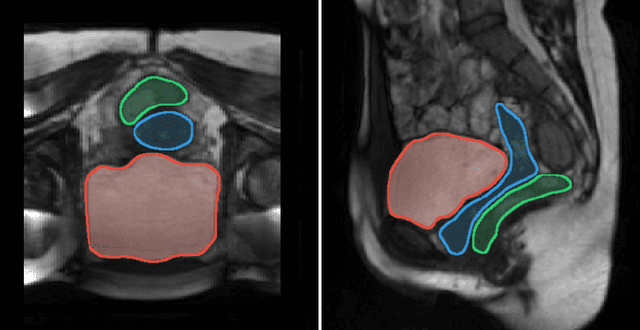

Background and Objective: Pelvic floor disorders are prevalent diseases and patient care remains difficult as the dynamics of the pelvic floor remains poorly known. So far, only 2D dynamic observations of straining exercises at excretion are available in the clinics and the understanding of three-dimensional pelvic organs mechanical defects is not yet achievable. In this context, we proposed a complete methodology for the 3D representation of the non-reversible bladder deformations during exercises, directly combined with synthesized 3D representation of the location of the highest strain areas on the organ surface. Methods: Novel image segmentation and registration approaches have been combined with three geometrical configurations of up-to-date rapid dynamic multi-slices MRI acquisition for the reconstruction of real-time dynamic bladder volumes. Results: For the first time, we proposed real-time 3D deformation fields of the bladder under strain from in-bore forced breathing exercises. The potential of our method was assessed on eight control subjects undergoing forced breathing exercises. We obtained average volume deviation of the reconstructed dynamic volume of bladders around 2.5\% and high registration accuracy with mean distance values of 0.4 $\pm$ 0.3 mm and Hausdorff distance values of 2.2 $\pm$ 1.1 mm. Conclusions: Immediately transferable to the clinics with rapid acquisitions, the proposed framework represents a real advance in the field of pelvic floor disorders as it provides, for the first time, a proper 3D+t spatial tracking of bladder non-reversible deformations. This work is intended to be extended to patients with cavities filling and excretion to better characterize the degree of severity of pelvic floor pathologies for diagnostic assistance or in preoperative surgical planning.